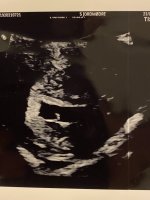

Aww, h*n ser ut som en liten bamsemumsLillegull! Alt bra og målene stemmer perfekt med 8 uker. Sterke hjerteslag

dagene fram til 9. august kan ikke gå fort nok!Lillegull! Alt bra og målene stemmer perfekt med 8 uker. Sterke hjerteslag

Så utrolig tydelig bilde! GratulererLillegull! Alt bra og målene stemmer perfekt med 8 uker. Sterke hjerteslag